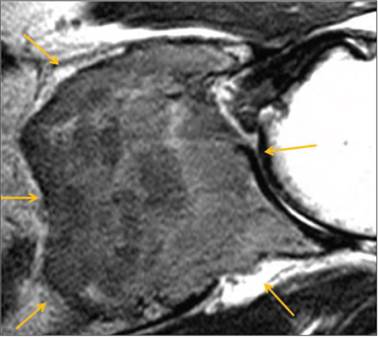

Inició en mayo de 2013 con dolor en hombro izquierdo con limitación a los movimientos de extensión y flexión, se automedicó con analgésicos con lo que mejoró, sin embargo, el dolor se incrementó en el mes de agosto del mismo año por lo cual acudió con un médico ortopedista quien le solicitó RM para descartar lesión de manguito de los rotadores (Figuras 2 y 3).

Figura 2 Resonancia magnética de escápula izquierda en corte sagital, ponderada en T1. Muestra neoplasia lobulada de bordes irregulares que invade la médula ósea (flechas).

Figura 3 Resonancia magnética de escápula izquierda en corte axial. Secuencia de T2; muestra neoplasia de aspecto heterogéneo que afecta a la médula ósea y desplaza estructuras musculares produciendo efecto de masa (flechas).

En el estudio de RM, la médula ósea de la escápula se observa un tumor lobulado, de contornos irregulares, mal definidos, con zona de transición larga, con patrón permeativo, de comportamiento hipointenso en el T1, iso-hiperintenso en el T2 e hiperintenso en la densidad de protones con saturación grasa. Esta imagen muestra pérdida de la continuidad de la cortical de la cavidad glenoidea hacia su aspecto anterior y se continúa hasta el proceso coracoideo que condiciona desplazamiento anterior e inferior del músculo subescapular, así como desplazamiento superior del tendón del supraespinoso.

El reporte de este estudio fue de imagen sugestiva de neoplasia primaria hacia la escápula izquierda que se continua hasta el proceso coracoides.